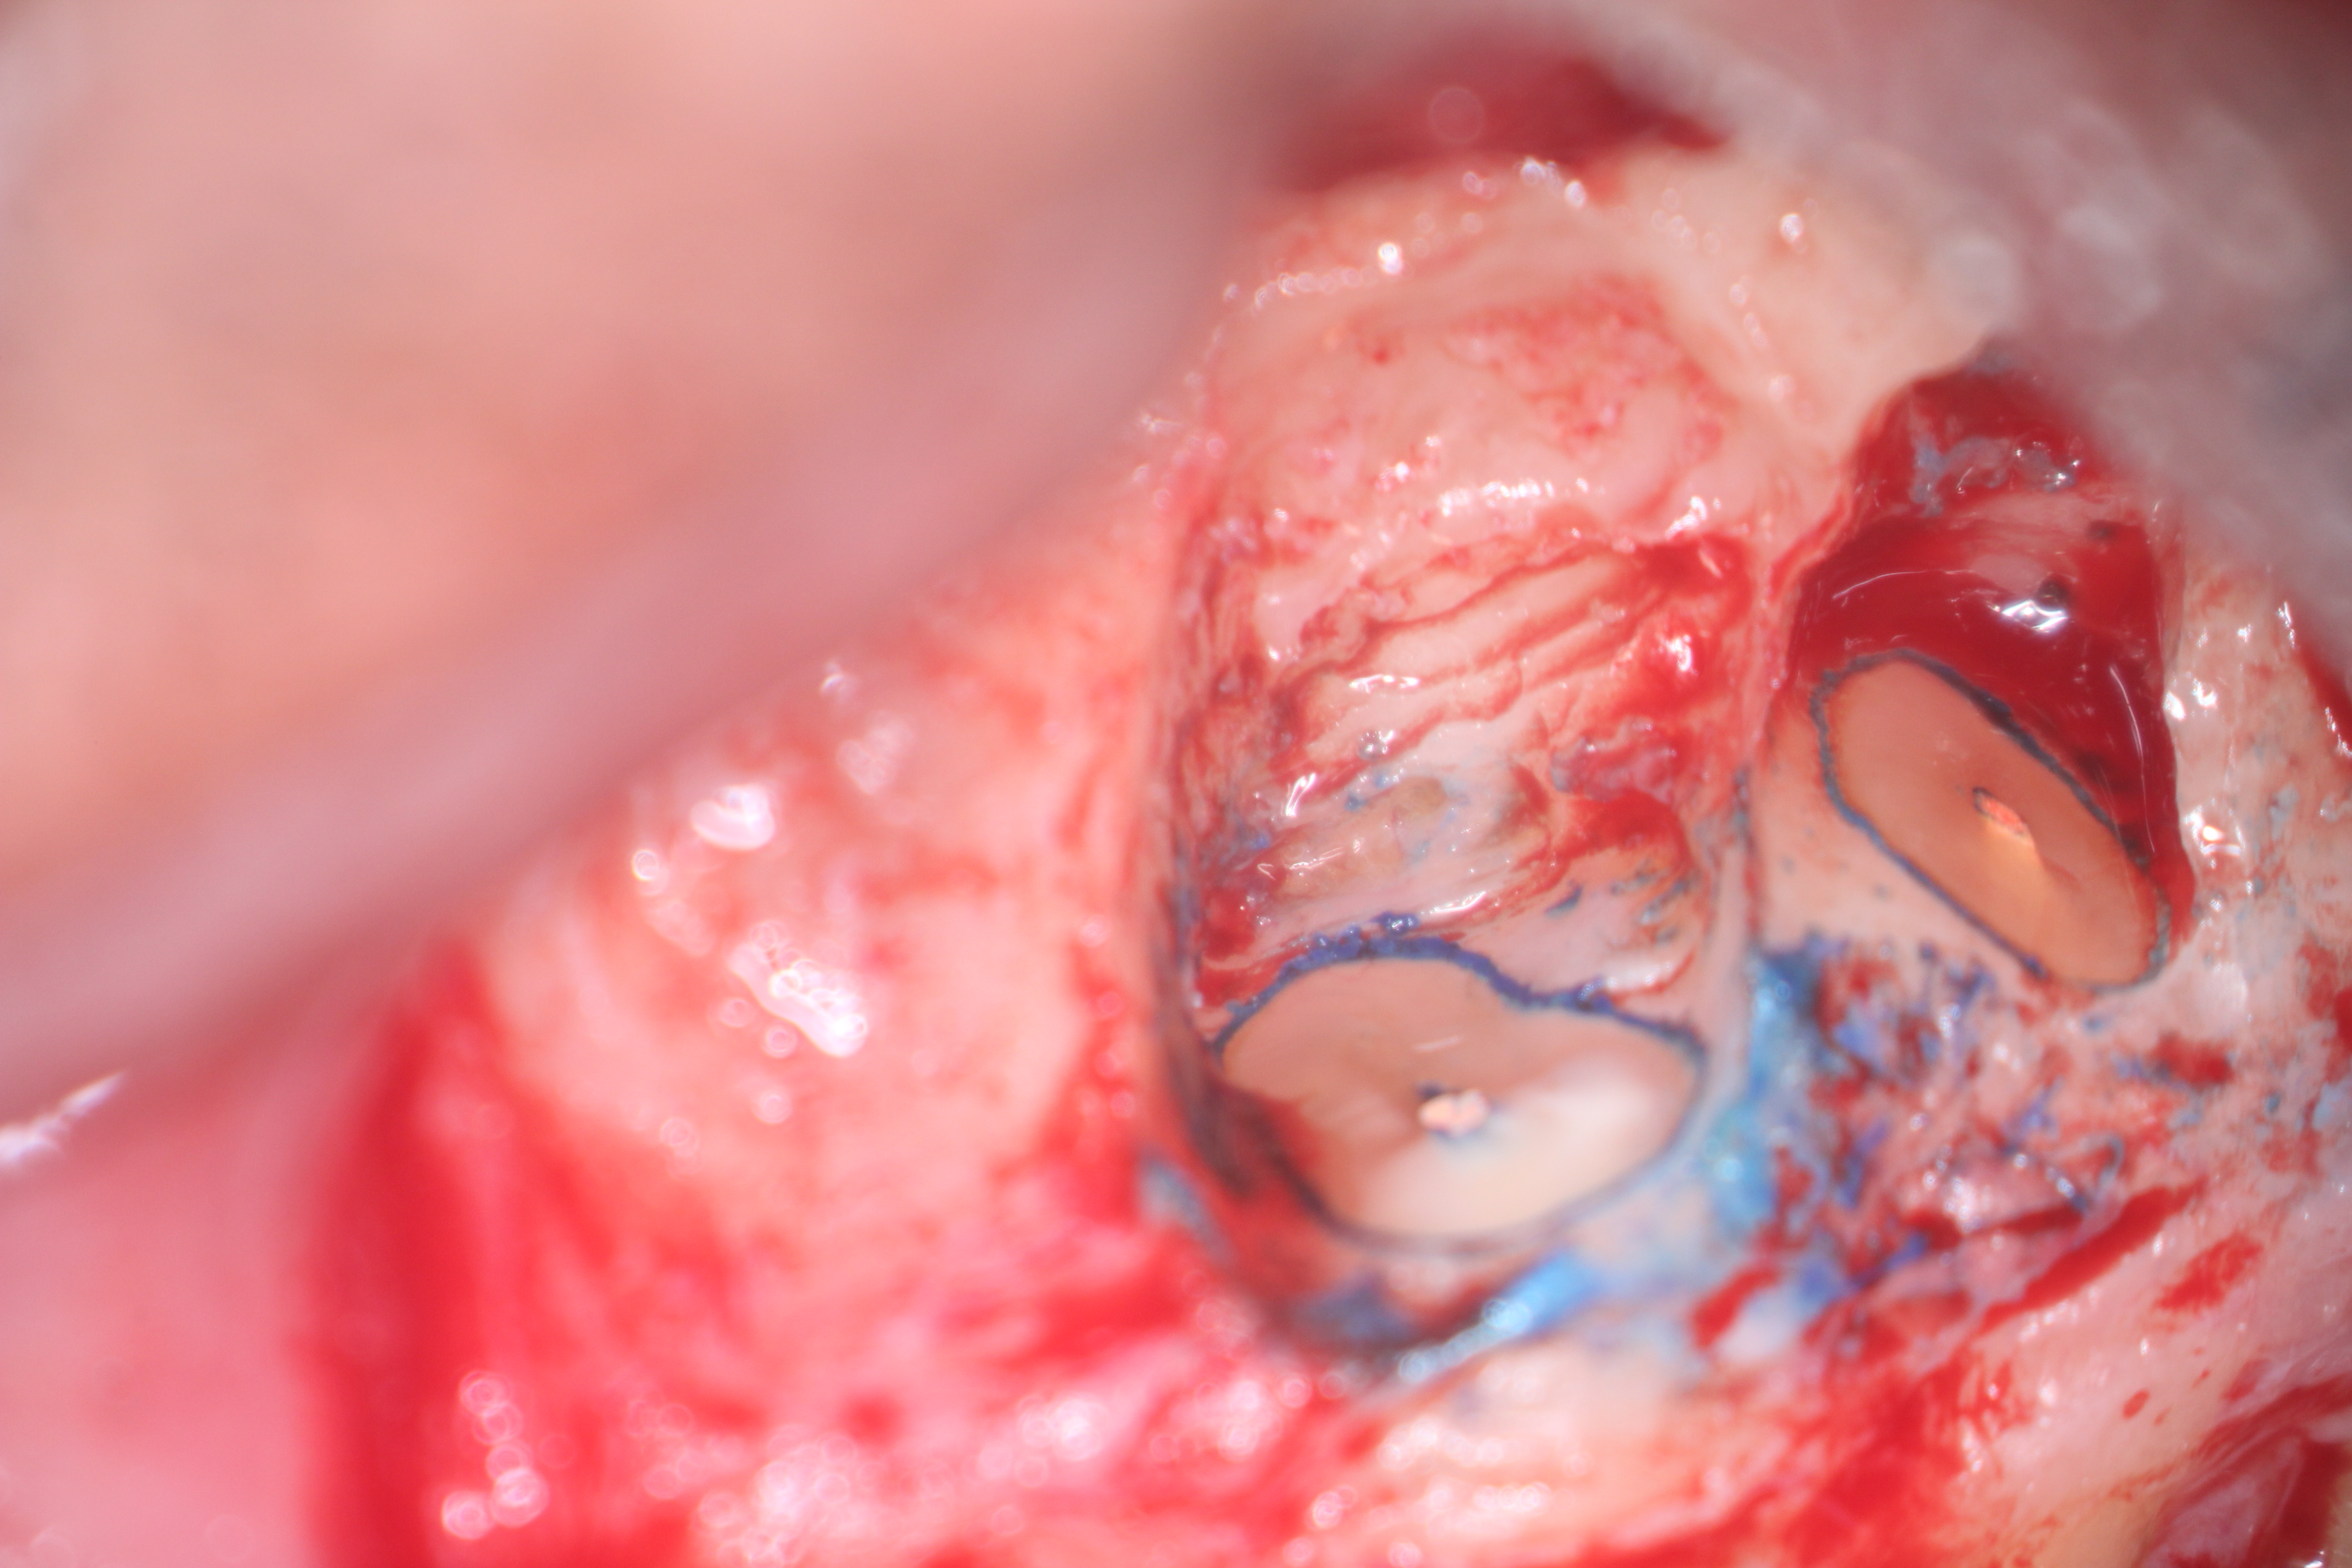

Fig 16. 3-mm root resection with methylene blue staining.

Figure 16

Clinical procedure: In the case of a root-end filling (Figure 15), once the apical 3 mm of the root has been resected (Figure 16) the canal system is then opened and cleaned with surgical ultrasonic tips to create the retro-preparation (Figure 17). After this is completed, the retro-preparation is dried and MTA is then placed and condensed in that space creating the retro-filling (Figure 18 through Figure 20).